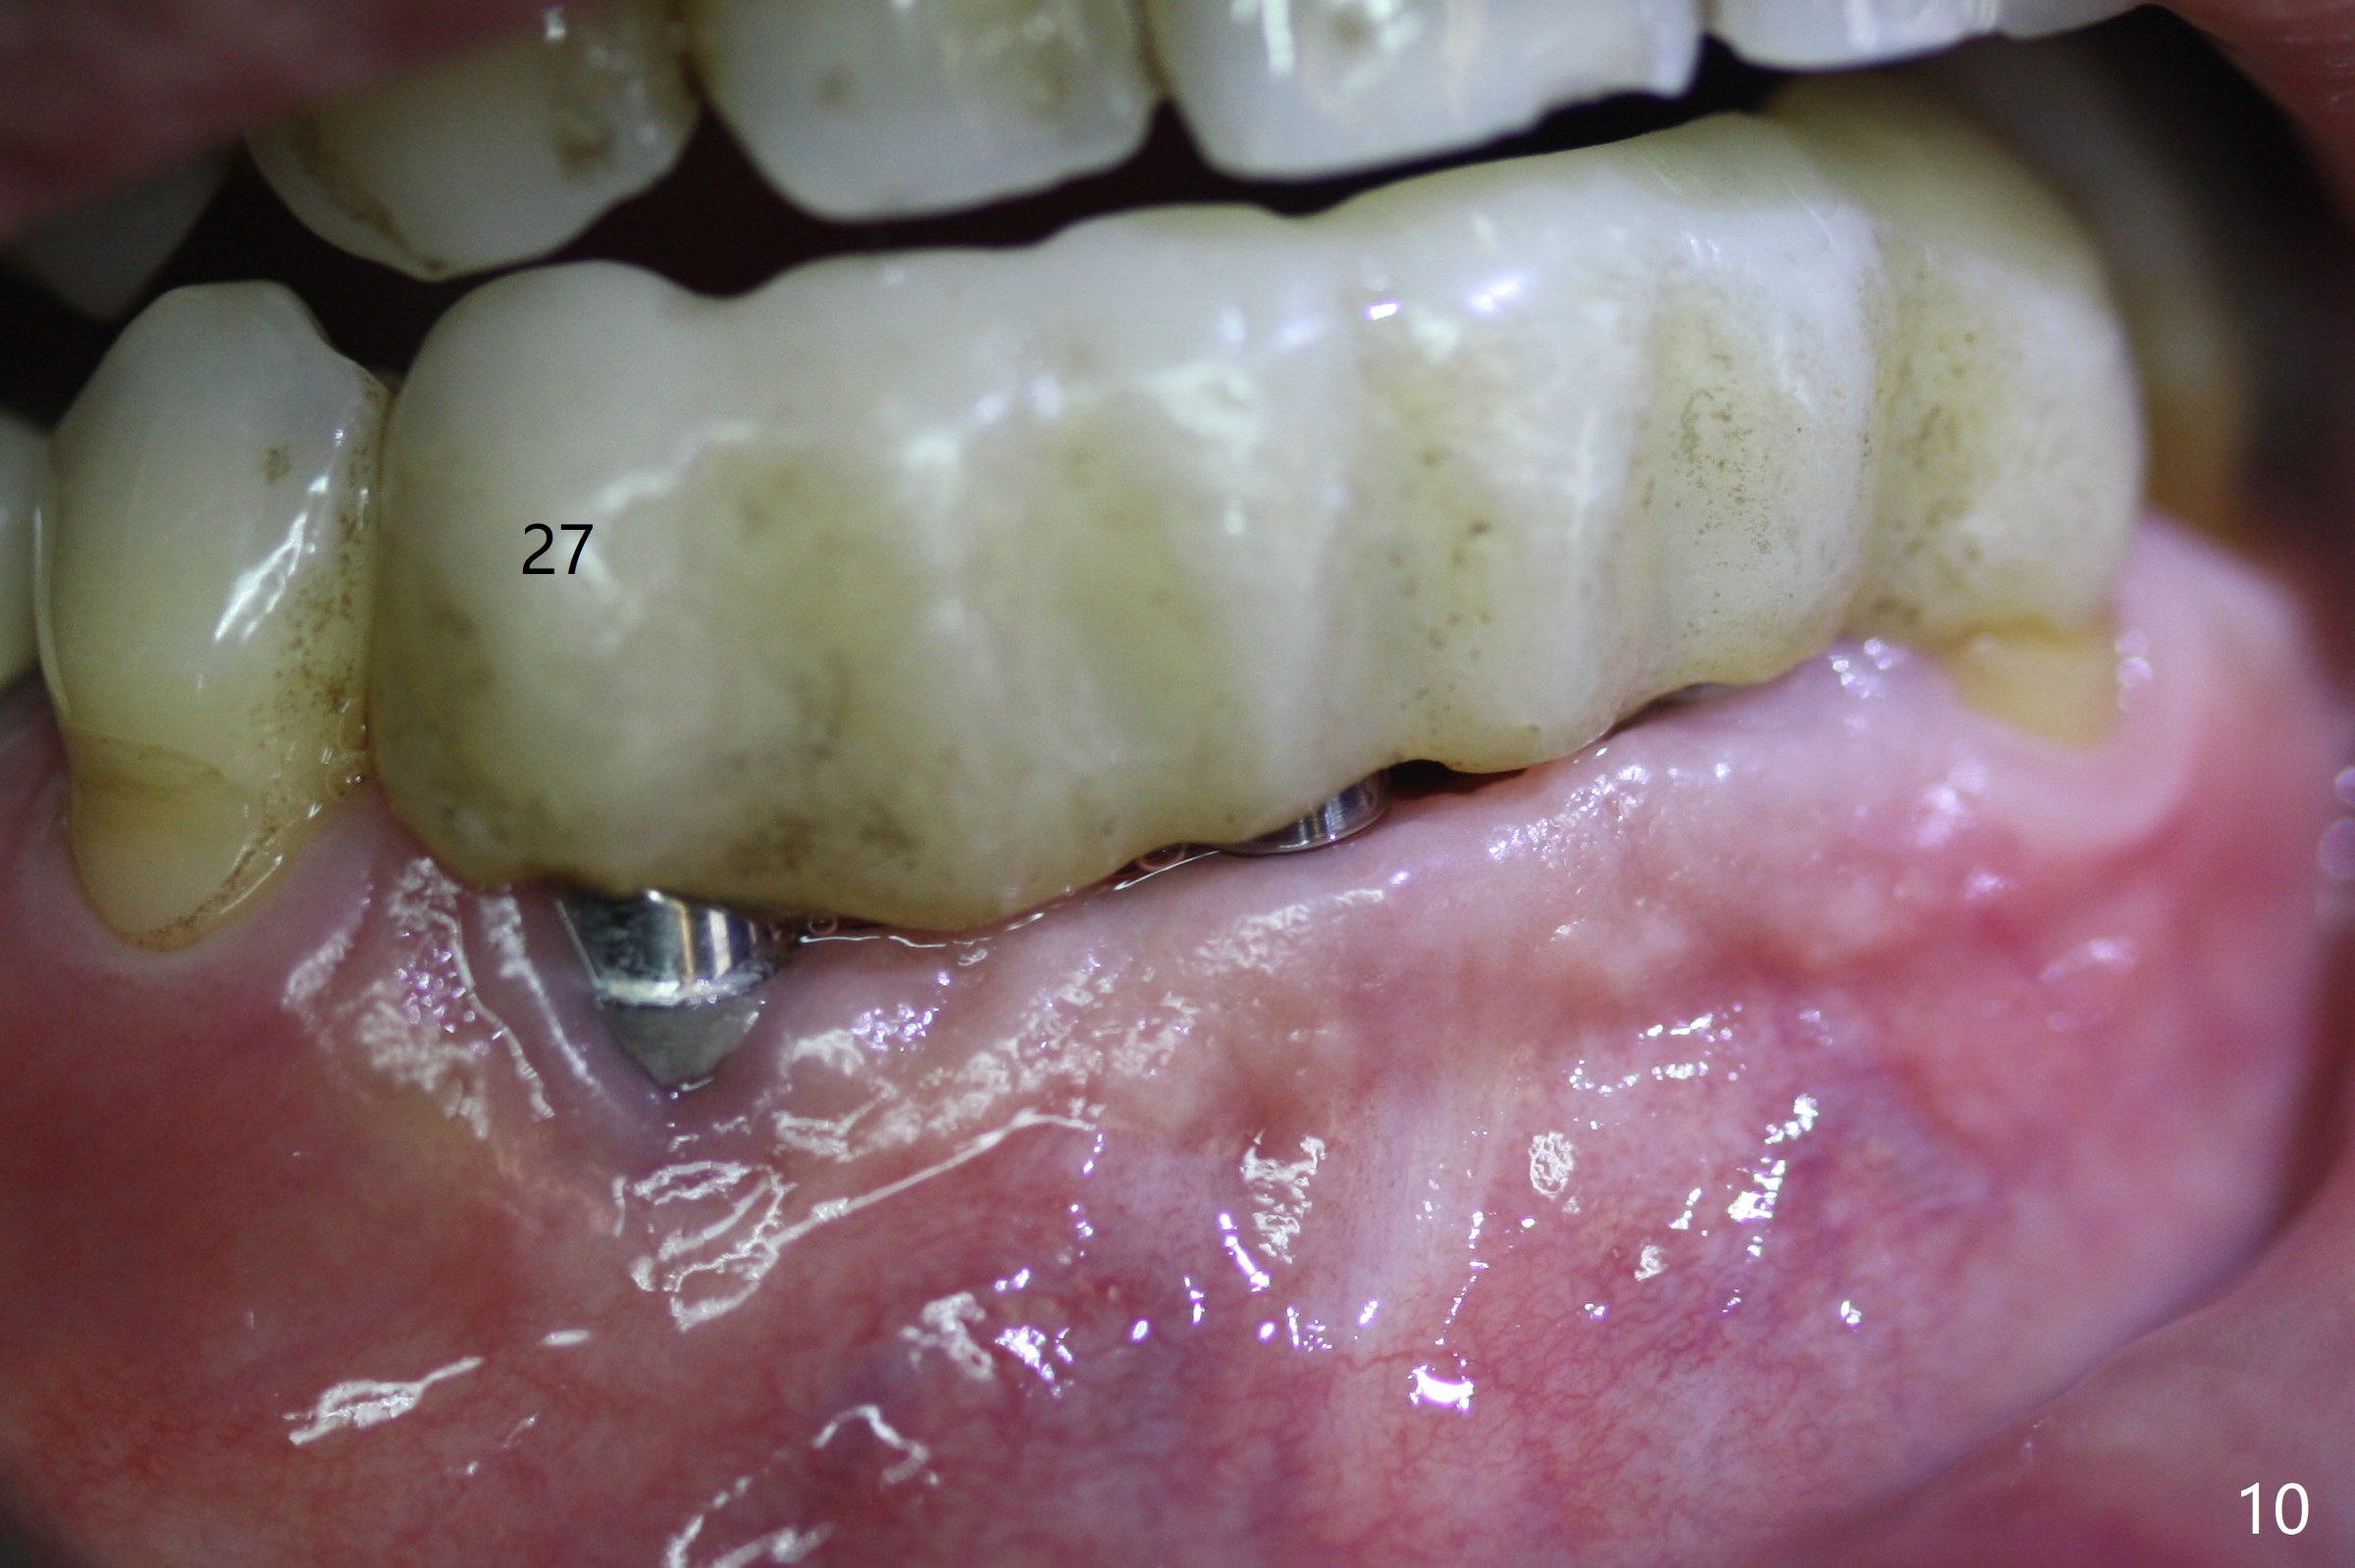

The mesial defect at #27 appears to have been repaired 8 months postop (Fig.8,9 *); there is no bone loss at 1-piece implant sites. The gingival recession seems to remain the same before and after removal of the provisional FPD (Fig.10,11). The bulging abutment at the cervix is less prominent when a straight abutment is used and prepared (Fig.12, 4.5x5.5(5) mm). There is no bone loss at #23, 25 and 27 sites 2.5 years post cementation (Fig.12-15), although the trajectory of the implants could be improved by using surgical guide (Fig.16-18).